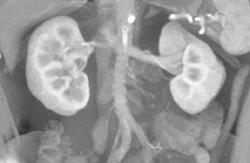

Bone Mets From Recurrent Renal Cell Carcinoma